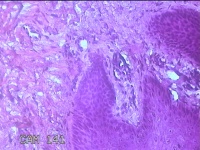

右侧足底结节

性别

男

年龄

41岁

临床诊断

鸡眼和胼胝

一般病史

发现右侧足底结节伴隐痛不适半年余。

标本名称

大体所见

灰白粉红色带皮肤样结节1x0.8x0.3cm一个,表面糜烂,切开结节呈实性,切面灰白粉红色,质硬。